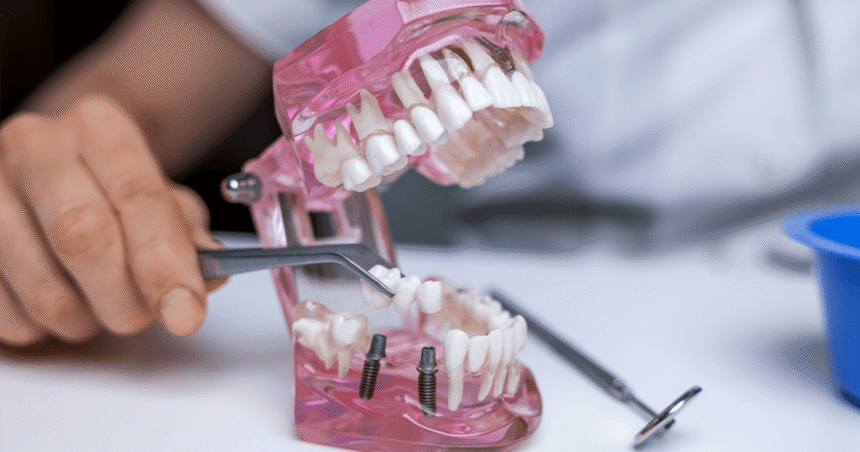

A dental implant is a small titanium post that acts like an artificial root. The post is gently placed into the jawbone where the old tooth once sat. Over the next few months, the bone bonds with the titanium in a process called osseointegration. This secure bond creates a foundation as strong as a natural root. Once healing is complete, a custom made crown is fixed on top. The result is a brand new tooth that can bite, chew, and sparkle just like the original. Because the implant is anchored in bone, it does not slip or click the way some dentures can. Patients often say they forget it is even there.

The first visit is relaxed and unhurried. Patients meet the dentist, share their goals, and have photos and scans taken. These images allow the team to plan exactly where the implant will sit and to check that nerves and sinuses are avoided. Once the plan is approved, the next appointment is set for the minor surgical stage. Local anaesthetic ensures the area is numb, and sedation is offered for nervous patients. The implant post is placed in a short procedure that normally takes less than an hour. Temporary crowns or bridges are fitted so no one leaves with a gap. Over the next three to six months the implant fuses with the bone. Patients can eat soft foods and carry on as normal. When healing is complete, a small connector called an abutment is attached and the final crown is fixed in place. Most people return to work the day after surgery and report far less discomfort than they expected.